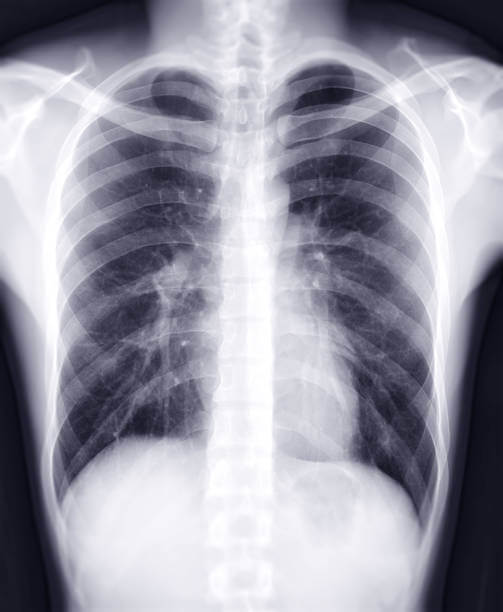

합병증 확인: 폐부종과 관련된 합병증 여부를 확인하기 위해 흉부 X-선, CT 스캔, 혈액검사 등이 수행될 수 있습니다. 이는 폐 이외의 다른 기관과 조직의 상태를 확인하는데 도움을 줍니다.

폐부종의 진단을 위해 다양한 검사가 수행될 수 있습니다. 이는 폐 기능 평가, 원인 파악 및 평가, 합병증 확인 등을 위한 목적으로 진행됩니다.

폐 기능 평가: 폐 기능을 평가하기 위해 폐기능 검사가 수행될 수 있습니다. 이는 폐의 체적, 체적 변화, 기도 통행능력 등을 평가하는데 도움을 줍니다.

원인 파악 및 평가: 폐부종의 원인을 확인하기 위해 심장 초음파, 심전도, 혈액 검사 등이 수행될 수 있습니다. 이는 심장 기능, 혈액 순환 상태, 심장질환 여부 등을 평가하는데 사용됩니다.